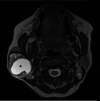

Figure 1. T2-weighted MRI (T2WI).

Image showing a well-defined lesion in the right parotid gland with a central homogeneous hyperintense component (*) suggestive of a cyst. Note the heterogeneous peripheral solid component with a few smaller microcysts within.